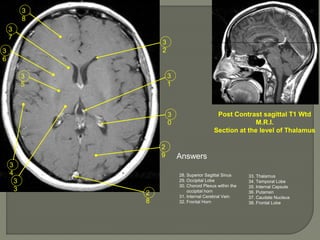

Post Contrast sagittal T1 Wtd

M.R.I.

Section at the level of Thalamus

Answers

28. Superior Sagittal Sinus

29. Occipital Lobe

30. Choroid Plexus within the

occipital horn

31. Internal Cerebral Vein

32. Frontal Horn

33. Thalamus

34. Temporal Lobe

35. Internal Capsule

36. Putamen

37. Caudate Nucleus

38. Frontal Lobe